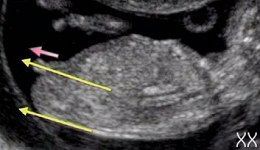

На сроке 12 недель врач УЗИ может сделать предположение относительно пола, порой оно чуть более точное чем 50/50

Правильная визуализация любой части плода зависит от многих факторов, таких как положение плода, количество амниотической жидкости и толщина брюшной стены. Такие удачные картинки как на фото слева получаются крайне редко. У кого больше?

На УЗИ, если ребенок хорошо повернулся, пол может быть определен на сроке 12 недель после зачатия (14 акушерских).

Определение происходит за счет анализа угла между половым бугорком и спинкой малыша.

На сколько точные результаты определения пола ребенка в первом триместре беременности.

Опытные УЗИ специалисты могут определить пол, измерив угол полового бугорка.

На 13 неделе процент ошибки составляет примерно 50% (из 100 мальчиков точно пол определен у 14), на 16 неделе определение пола уже более точное.